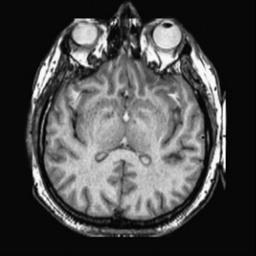

To demonstrate the effectiveness and efficiency of the proposed image fusion method , we conduct a set of comparative experiments on three image datasets. The first is composed by 8 pairs of multi-modal medical images and the second one contains 15 pairs of multi-focus gray or color natural images. These two datasets are often used in many related papers and some examples are shown in Figure 3(a) and Figure 3(b). The third one is a new multi-focus cervical cell image dataset collected by ourselves, which consists of 15 groups of color images and each group contains a series of multi-focus cervix cell images with size of or , etc. Some source examples are shown in Figure 3(c). Our source code implemented in C++ along with the new multi-focus cervical cell image dataset is available online.

We first evaluate the performance of the proposed method under varying total number of octaves and number of layers sampled per octave. The fused images of a pair of multi-modal medical images with different and are shown in Figure 4. In this example, on the one hand, when only 1 or 2 octaves are involved in constructing the DoG pyramid, the fused images fail to keep the integrity information of large size objects (e.g. eyeballs), while by increasing the value of , the integrity information of eyeballs is preserved. On the other hand, although not as significant as the increase of octave numbers , the fused image can contain more details by the increase of layer numbers . The corresponding objective quality metrics are shown in Figure 5. As shown in Figure 5(a), most of the metric values are improved as the number of octaves increases with the fixed layer numbers 3 in the global tendency and each of them tends to be stable when the number of octaves is 5. To get a relatively good quality from Figure 5(b), we can notice that some of the metric values can get a good performance when the number of layers is 3, such as the MI, SSIM, QI and VIF, though there are only a little change of all the metric values by increasing the number of layers with the fixed octave numbers 5. Because it will result in more computation burden with the increase of the value and , and for different kinds of source images, there are different performance with the diverse parameter settings. To get a trade-off between them in our experiments, we set for the multi-modal dataset, for the natural datasets and for the multi-focus cell dataset, respectively.

Figure 6 shows the fused images obtained by different methods with the multi-modal source images shown in Figure 3(a). As shown in these figures, the proposed method can produce images which preserve the complementary information of different source images well. Moreover, due to the scale-invariant structure saliency selection, our method can keep the integrity information of large size objects and the visual details simultaneously. Although the fused image generated by other methods can also capture the details to some extent, all of them fail to keep the integrity information of large size objects such as the eyeballs. Furthermore, from Figure 6(k)-6(t), the DTCWT, GFF, IM and NSCT methods may decrease the brightness and contrast while the proposed method can preserve these features and details without producing visible artifacts and brightness distortions.